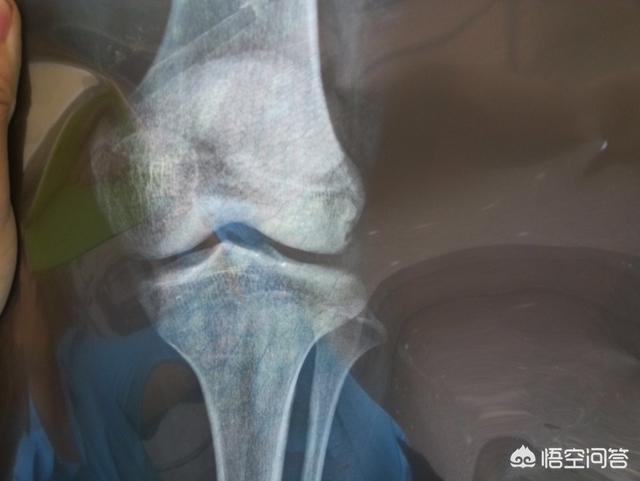

Medizinisch gesehen kann man nach der Menstruation noch größer werden, solange sich die Epiphyse nicht geschlossen hat. Wenn Sie wirklich wissen wollen, ob Sie noch größer werden können, gehen Sie am besten ins Krankenhaus und lassen Sie Ihr Knochenalter mit einem Ultraschall untersuchen. Solange Ihr Knochenalter Ihr Alter nicht übersteigt, haben Sie das Potenzial, größer zu werden.

Deshalb, wenn das Mädchen hat seit einem Jahr menstruiert, nach dem normalen ist bereits späte Entwicklung, können Sie das Kind zu einem Knochenalter zu überprüfen, wissen, ob das Kind Epiphyse geschlossen ist, wenn es geschlossen wurde, dann ein halbes Jahr nicht wachsen, was bedeutet, dass aufhören zu wachsen größer.